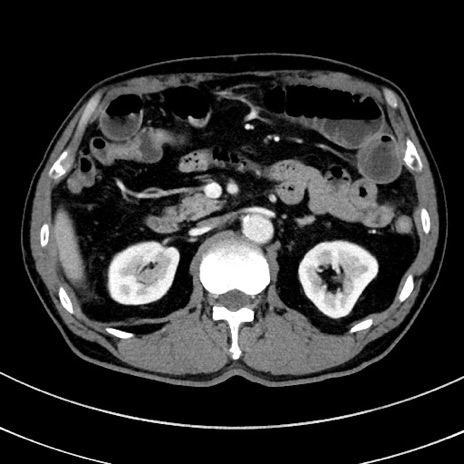

症例8(横断像)

【症例】 60歳代男性

【主訴】 黒色吐物

【現病歴】 4日前から嘔気自覚、2日前の朝食後にも嘔気あり、自分で手で嘔吐反射起こし嘔吐したところ血が混ざっていたため受診。

【既往歴】 5年前汎発性腹膜炎を伴う急性虫垂炎で手術、高血圧、前立腺肥大症、高脂血症

【身体所見】 腹部正中に手術癩痕あり 腹部平坦・軟圧痛なし膨満感あり

【データ】WBC 8400、CRP 4.54